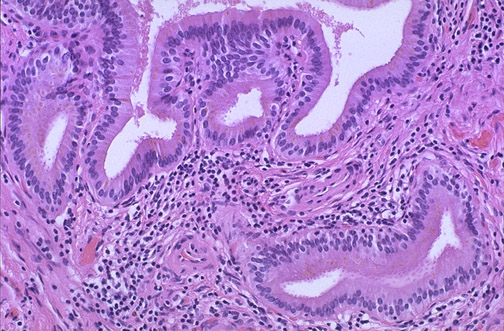

Chronic inflammatory cell infiltrates are seen here, typical for chronic cholecystitis. The gallbladder may be grossly enlarged, normal, or small in size, but there is unlikely to be obstruction with chronic cholecystitis.